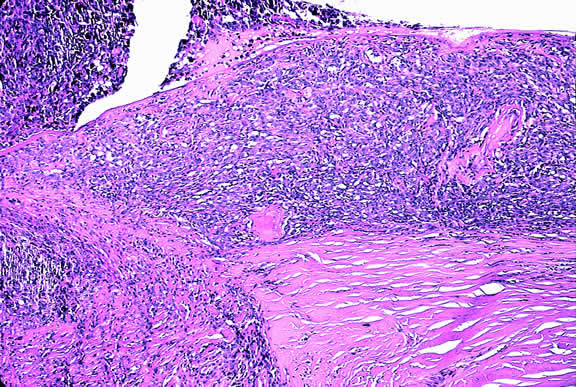

Histopathology

The cells comprising uveal melanoma constitute a biologic spectrum comprising bland spindle A melanoma cells at one end and wildly anaplastic epithelioid cells at the other. The term spindle cell is derived from the fusiform or spindled configuration of the cells' cytoplasmic outline. They are bipolar in shape, and many have long tapering processes that occasionally are highlighted when individual pigmented cells are seen in a largely amelanotic tumor. Spindle cells grow in a syncytial fashion forming interweaving fascicles of parallel oriented cells (Fig. 30). The cells can be pigmented or nonpigmented. Two types of spindle cells are recognized; spindle A and spindle B. These are distinguished by their nuclear characteristics. Spindle A nuclei are tapering ovals or cigar-shaped and have finely dispersed chromatin (Fig. 31). If a nucleolus is present, it usually is inconspicuous. Many spindle A cells have a longitudinally oriented chromatin stripe that actually is caused by a fold in the nuclear membrane. The nuclei of spindle B cells have distinct nucleoli and coarser chromatin and tend to be plumper and more oval in shape (Fig. 32).

Fig. 30. Amelanotic spindle cell melanoma. Tumor is composed of interweaving fascicles of spindle cells. Photomicrograph shows longitudinally and transversely sectioned fascicles. (Hematoxylin-eosin, × 100.)